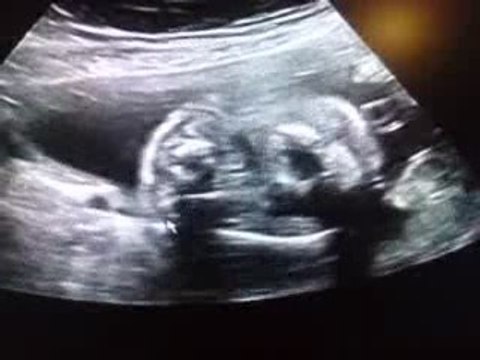

grossesse, mois